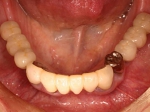

上部装着後のレントゲン像上部装着後のレントゲン像上部装着後のレントゲン像 術前口腔内写真術前口腔内写真術前口腔内写真 術後口腔内写真術後口腔内写真術後口腔内写真、食事がおいしくなったと非常に満足されている。